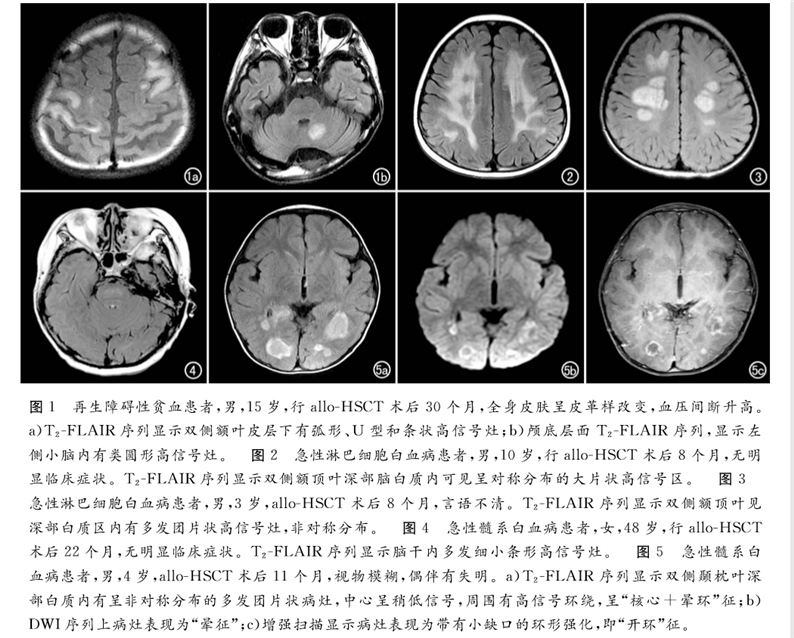

北京陸道培醫(yī)院影像科發(fā)表題為《血液病異基因造血干細(xì)胞移植后中樞神經(jīng)系統(tǒng)慢性移植物抗宿主病的MRI表現(xiàn)》的論文,該論文刊登在中文特種醫(yī)學(xué)類核心期刊《放射學(xué)實(shí)踐》2019年12月第34卷第12期。

論文回顧性分析了2013年6月—2017年12月北京陸道培醫(yī)院確診為allo-HSCT后并發(fā)中樞神經(jīng)系統(tǒng)慢性移植物抗宿主病的12例血液病患者的臨床和影像學(xué)資料。得出結(jié)論,MRI是發(fā)現(xiàn)血液病異基因造血干細(xì)胞移植(allo-HSCT)后并發(fā)中樞神經(jīng)系統(tǒng)慢性移植物抗宿主病的有效手段,可以提高對本病的診斷及鑒別水平,為臨床制訂佳治療方案提供幫助。